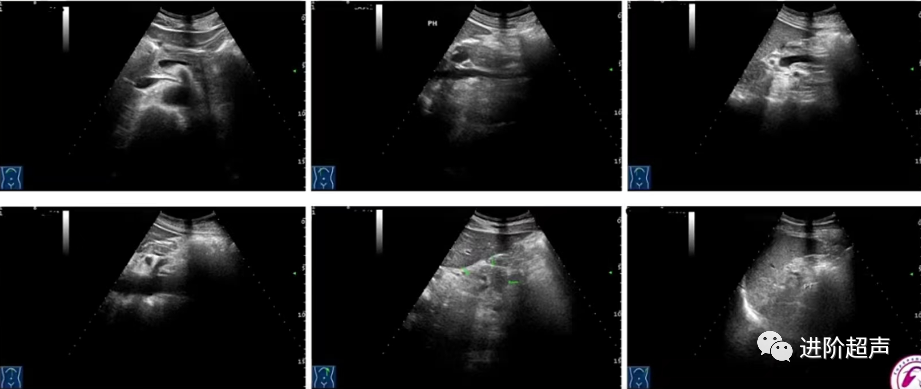

正常胰腺切面扫查

胰腺的长轴切面,胰头、颈、体、尾部的短轴切面,以及左肋间通过脾窗的胰尾切面

胰体占位

3

胰尾占位

显示胰腺长轴灰阶图像1张

胰腺长轴灰阶图像 (箭头所示)

IVC:下腔静脉 AO:腹主动脉

显示胰腺病变的灰阶图像2张 (应为不同角度切面下的图像,建议横切面+纵切面)